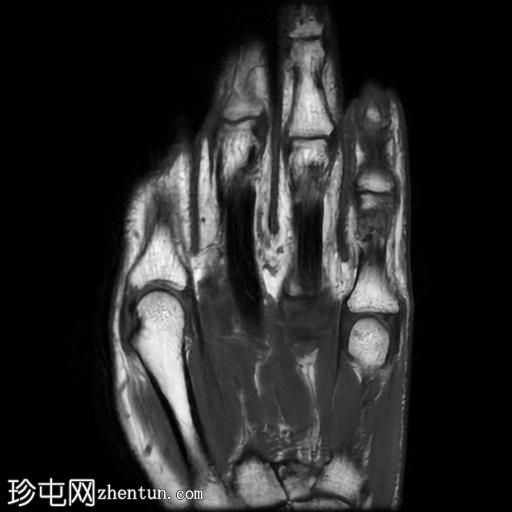

MRI

矢状位

T1加权像

冠状位PD脂肪抑制像

冠状位

第五指小指伸肌腱远端纤维完全撕裂,伴远端指间关节屈曲畸形。

撕裂肌腱近端位于第五指中节指骨头附近,止点与近端撕裂处之间约有4毫米的间隙。

患者左手受伤,导致第五指小指伸肌腱远端止点纤维完全撕裂,并伴有槌状指畸形。